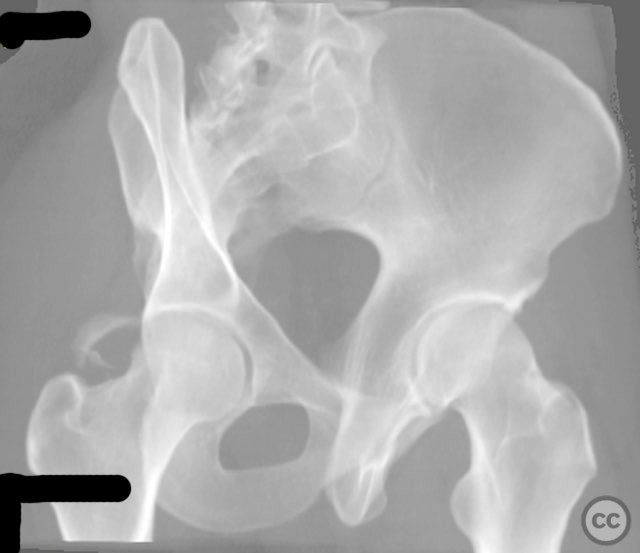

Clinical and radiological findings:  A 20-year-old male collegiate basketball player sustained a displaced right posterior wall (PW) acetabular fracture-dislocation during practice. Initial AP pelvic radiograph demonstrated a reduced femoral head with a displaced posterior wall fragment. Axial CT imaging revealed a large, peripherally located PW fragment with significant displacement, impaction into the abductor muscle mass, and no intra-articular comminution. Obturator oblique radiographs and intraoperative fluoroscopy under anesthesia demonstrated mechanical obstruction to passive abduction at 10–20 degrees due to the relationship between the displaced PW fragment and the greater trochanter.

Planning remarks:  The preoperative plan was for open reduction and internal fixation of the posterior wall fragment via a Kocher-Langenbeck (KL) approach. The technical plan included careful dissection to avoid further devascularization of the fragment, direct fragment mobilization, reduction, and fixation using a spring-hook implant for fragment capture and a supporting reconstruction plate placed medial to the hook tines.